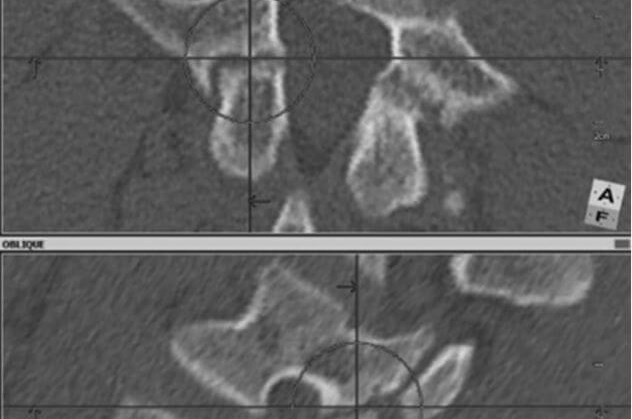

• Spondylolysis

Spondylolysis

Spondylolysis is a condition that in the vast majority of cases is diagnosed in young and very physically active people. It practically does not occur in people who are not physically active, spending most of their time, for example, at the computer. This condition is due to the specific nature of movement, but also to the fact that the bone is not mature and is not as mechanically strong as we would...

• Spondylolisthesis

Spondylolisthesis

Spondylolisthesis is a condition in which one vertebra moves forward in relation to the other. Among patients, there are two main groups: younger people, statistically under the age of 50 (with 30-40 year olds as a rule), and patients over the age of 50 (as a rule, they are around 60-70 years old).